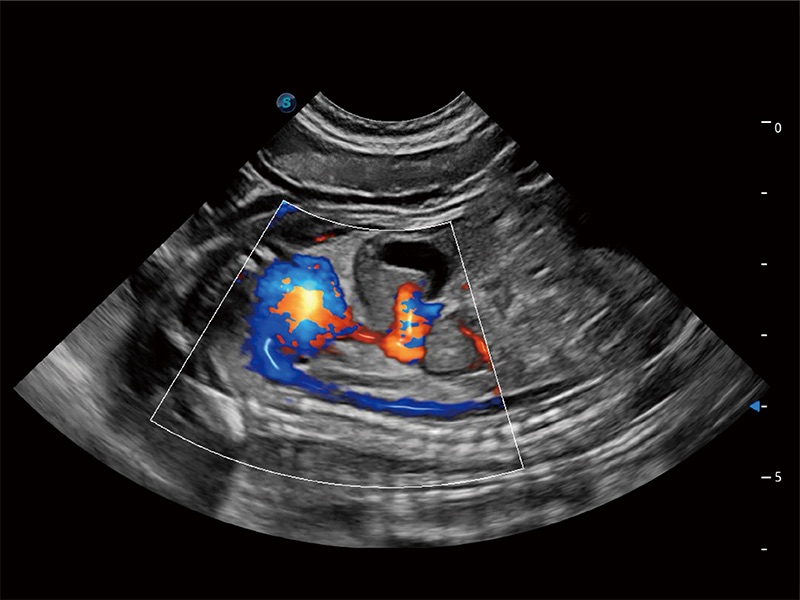

ProPet 80 配备了丰富的心脏探头群、先进的成像技术和专业的心脏测量工具,可帮助动物医生为不同体型和生理结构的动物提供心脏和心肌功能的全面评估。

高性能和先进的临床应用工具可以为动物医生提供临床信心。ProPet 80 搭载了先进的腹部和浅表应用工具,帮助医生在日常临床实践中发挥前所未有的作用。

极大提升超低速微细血流的检出能力,同时更精准地滤除软组织和超声信号,为兽用医生提供以往无法通过常规血流获得的疾病诊断信息。